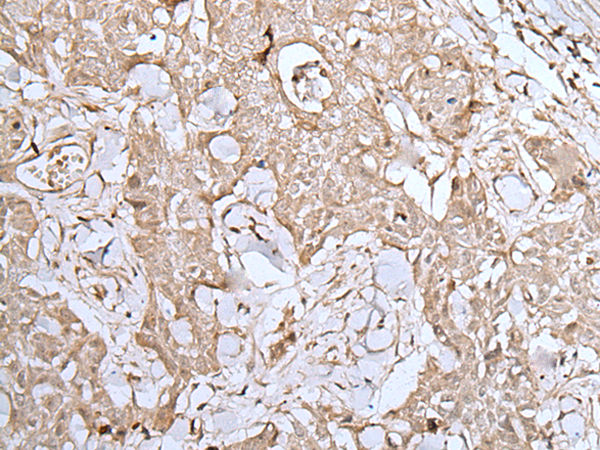

IHC positive control: |

Human lung cancer and human brain |

IHC Recommend dilution: |

25-100 |